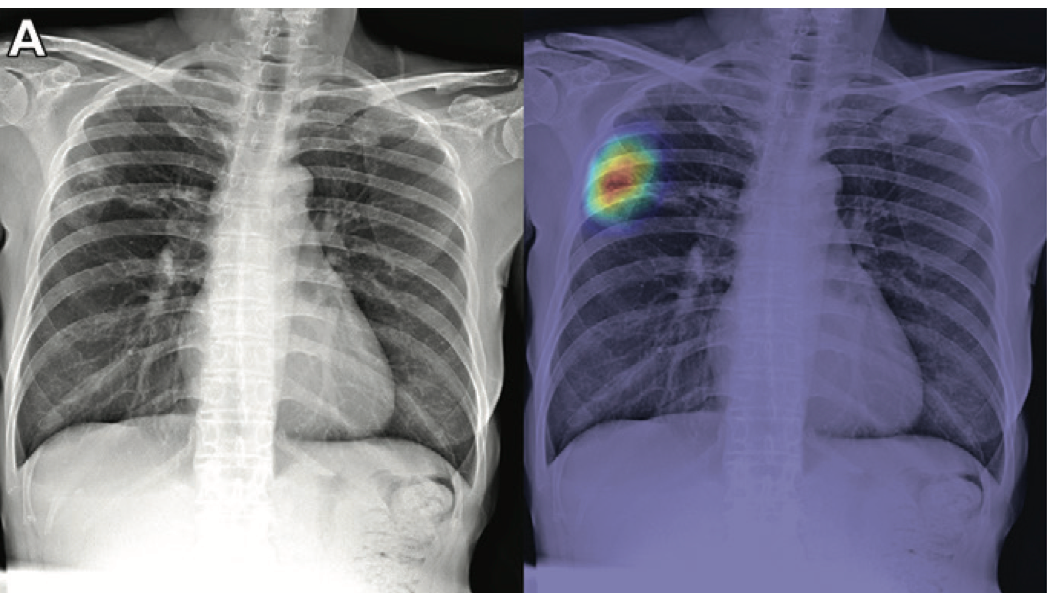

Both board-certified radiologists and radiology residents more appropriately suggested chest CT follow-up when using artificial intelligence with chest X-ray.

New deep learning tool is designed to help radiologists evaluate chest X-rays regardless of where they work.

Research shows artificial intelligence models rely on shortcuts for detecting COVID-19.

Study results show DCNN can use imaging biomarkers to predict sex, potentially confounding the accurate prediction of disease.